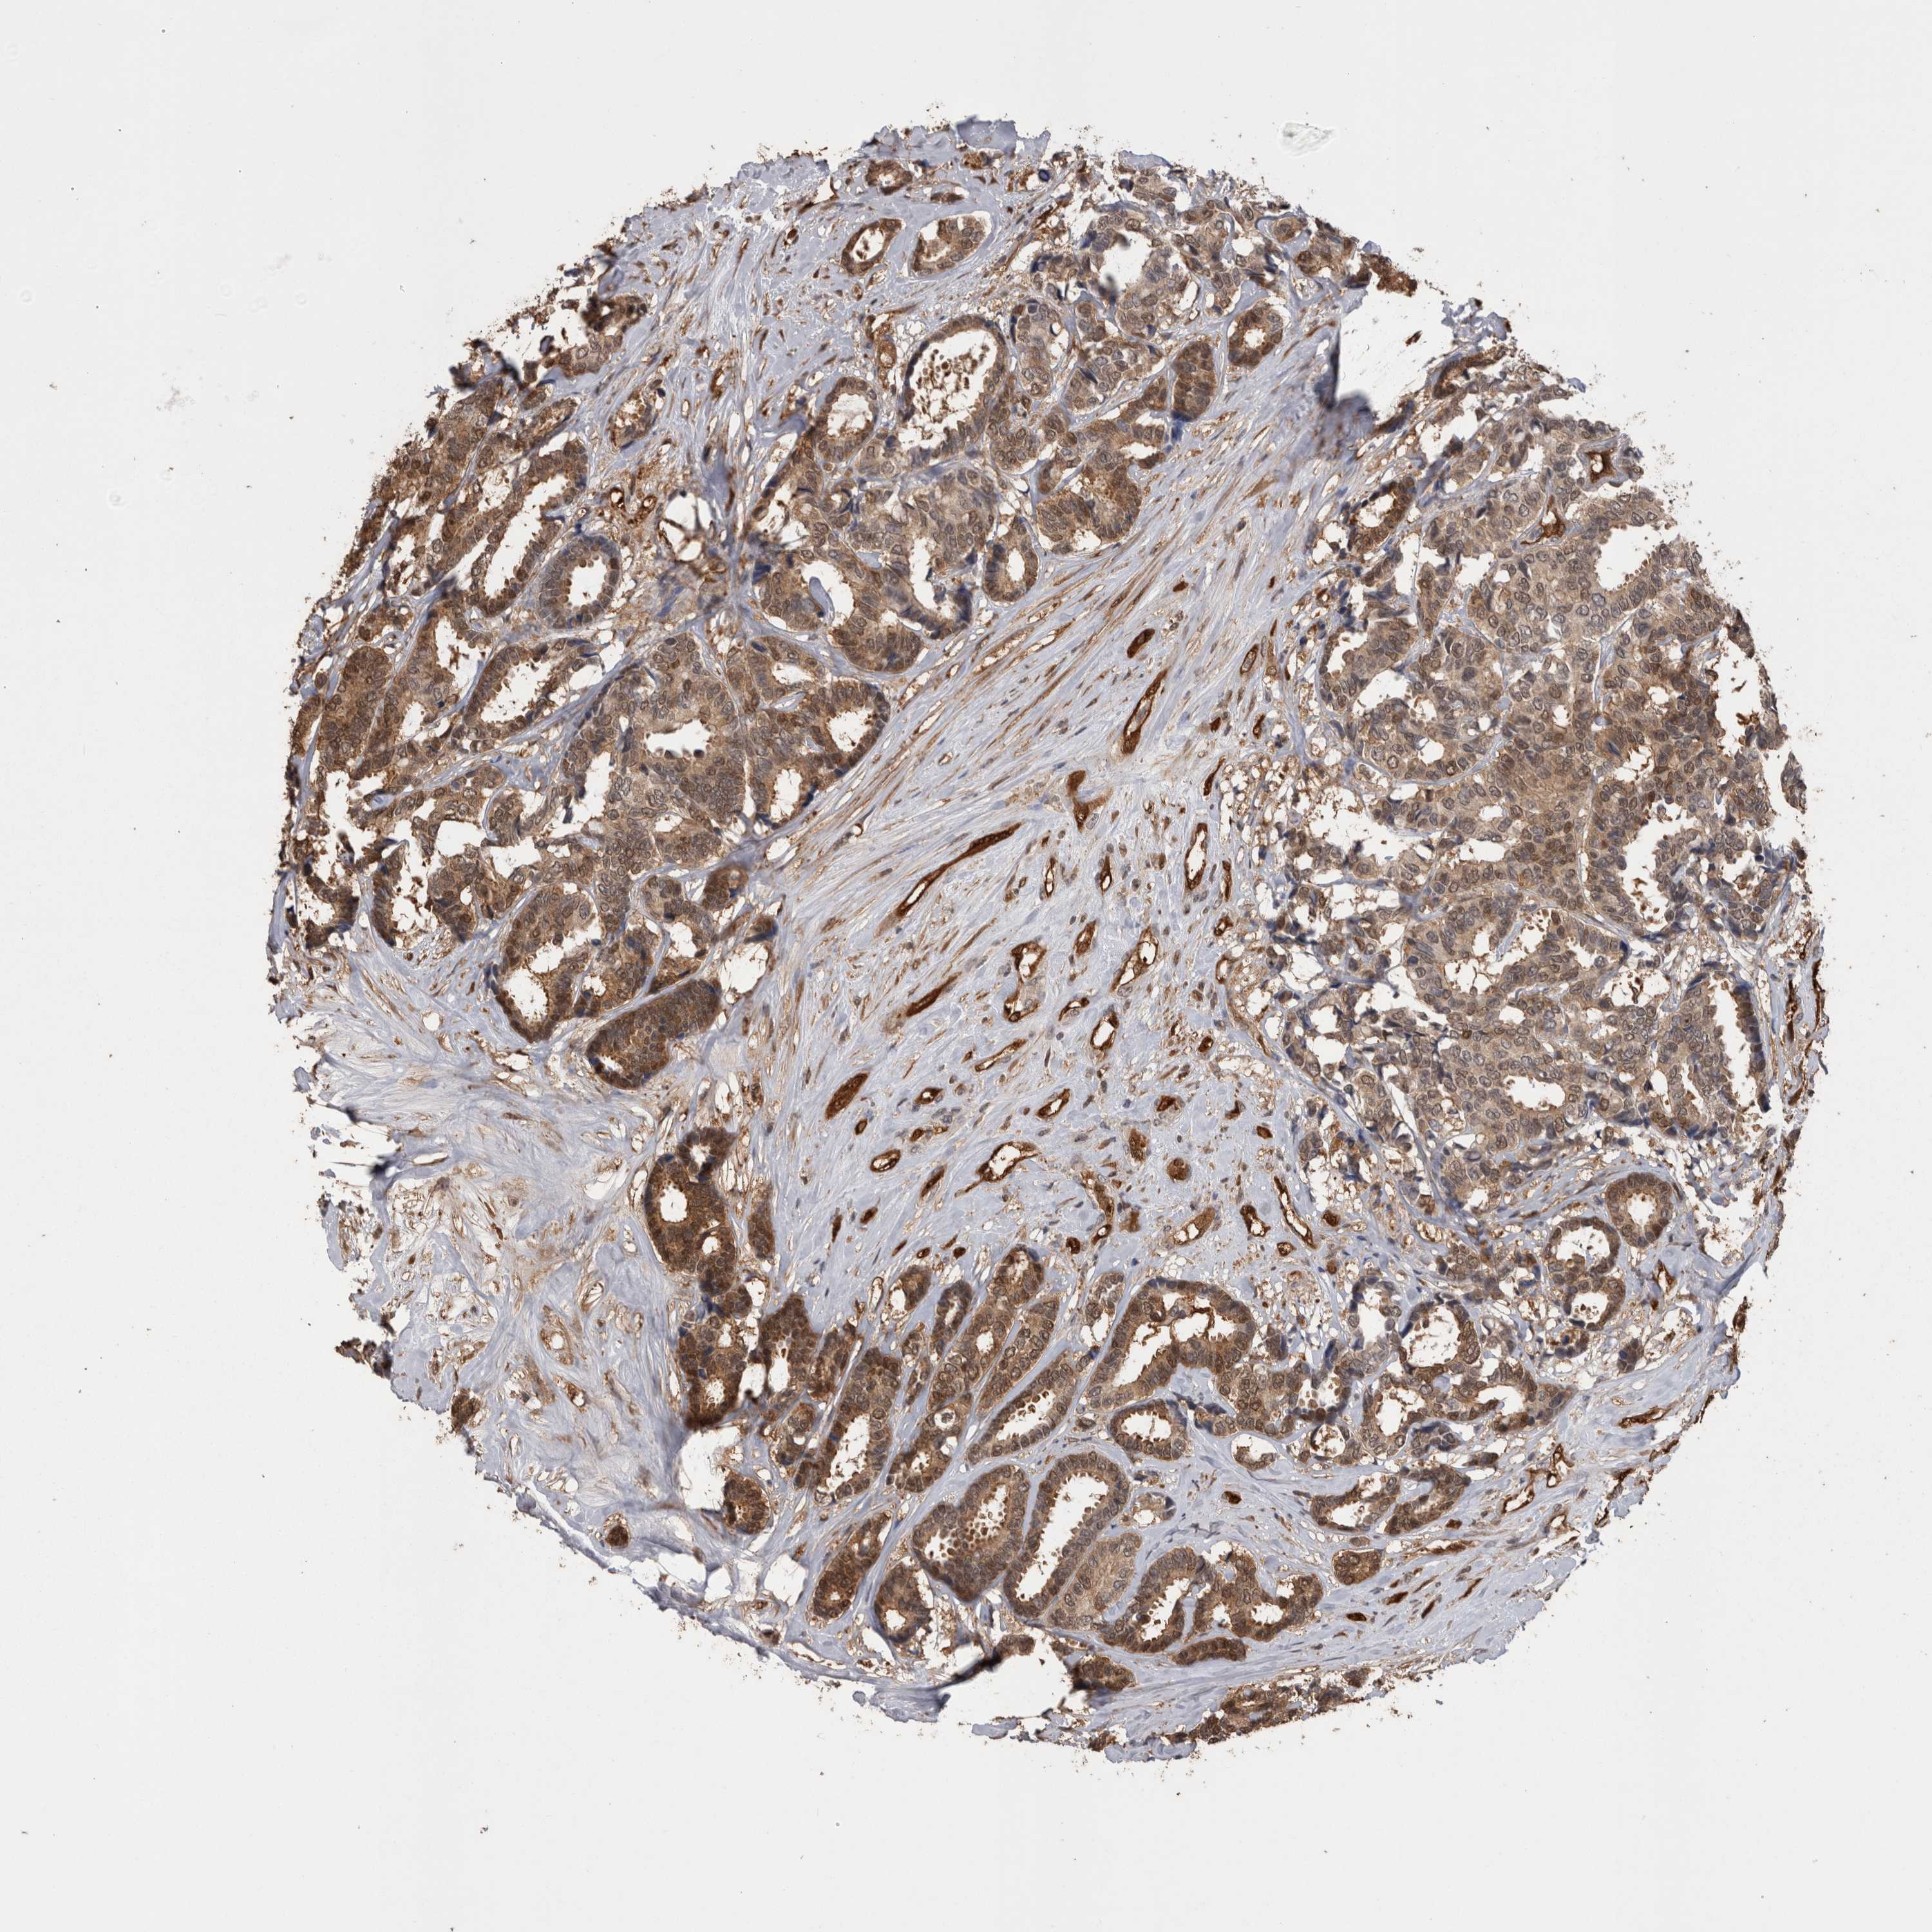

CANCER BREAST CANCER Show tissue menu

BRCA TCGA BRCA VALIDATION PROTEIN EXPRESSION